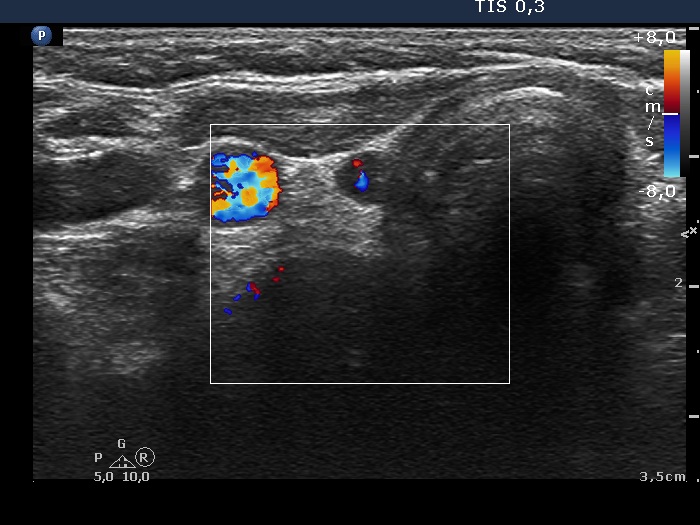

The operated thyroid - case 775 (ultrasonographic picture 3)

Right lobe, transverse scan, color Doppler method. Although the vascularization is not specific, it proved that the small hypoechoic area is indeed thyroid tissue.